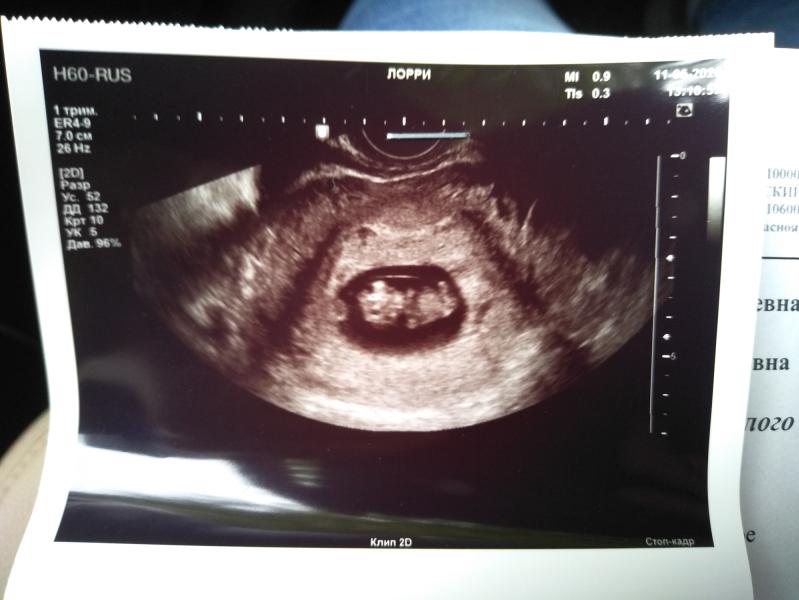

Для истории. Так как у меня неделю уже ехала крыша на предмет того что у меня пропали признаки беременности, а сегодня заболел живот. А советы не накручивать мне не помогали, я решила для успокоения своих нервов съездить на УЗИ. Оказалось всё в порядке. Я паникер. Но лучше перебдеть конечно. Муж послушал сердцебиение и посмотрел человека а там было на что посмотреть. Голова руки ноги.